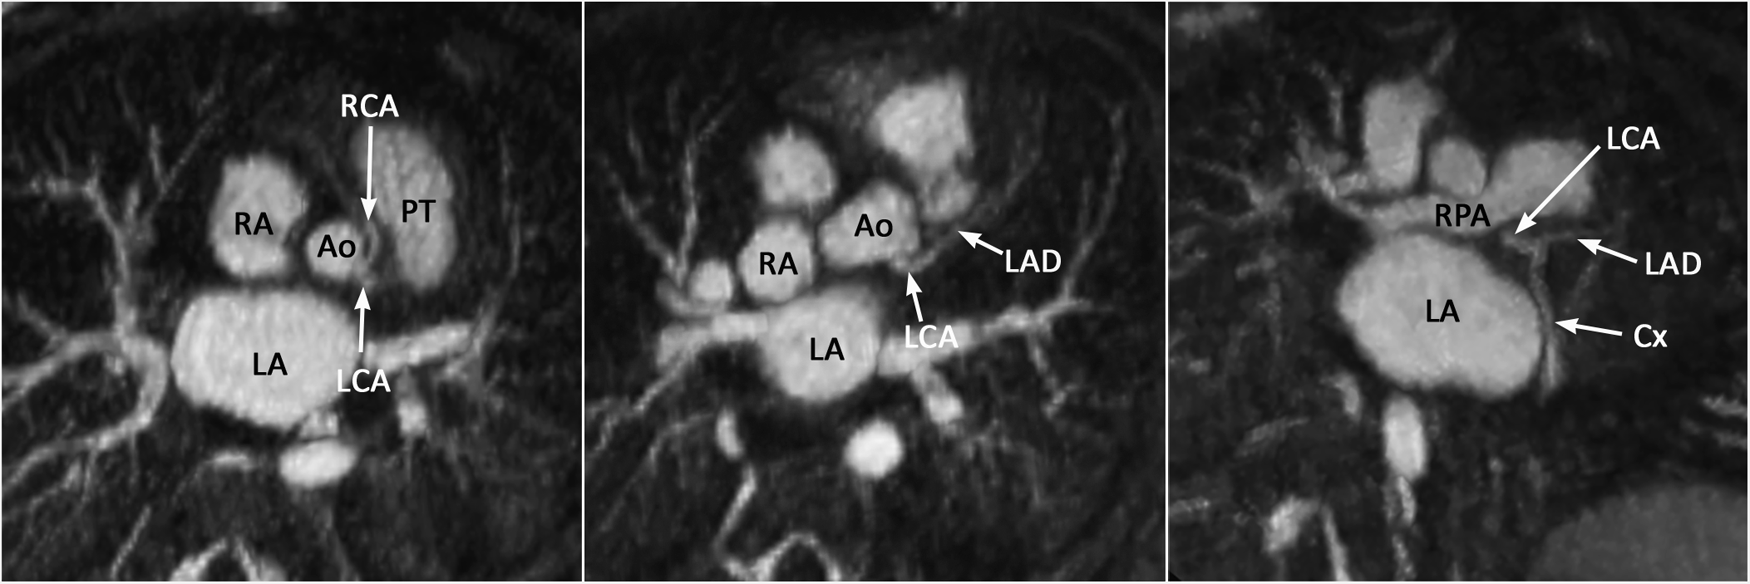

Figure 13

(Case 12). Common origin of the left (LCA) and right (RCA) coronary arteries from the sinotubular junction above the left coronary sinus. The RCA takes an interarterial course. An acute angle of its origin is highly suggestive of an intramural course. Ao, aorta; Cx, circumflex coronary artery; LA, left atrium; LAD, left anterior descending coronary artery; PT, pulmonary arterial trunk; RA, right atrium.